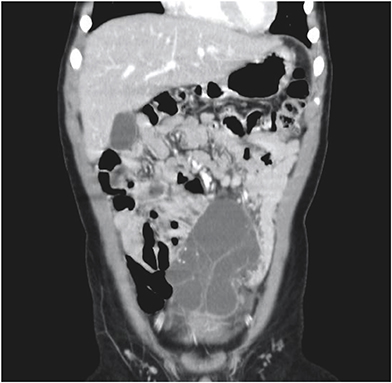

All patients underwent abdominal ultrasonography and computed tomography (CT) scans. In patient No. 7, these modalities showed a cystic mass, 9 cm in size, with multiple septa in the lower abdomen (Figs. 1, 2). An abdominal CT scan of patient No. 9 showed a huge multiloculated cystic mass with a septum; this mass occupied nearly the entire abdominal cavity and caused the displacement of the bowel to the left posterior abdomen.

Fig. 2

Abdominal computed tomography scan with intravenous contrast enhancement of patient No. 7, showing a multiloculated cystic mass with a thin wall occupying the lower abdomen.

Fig. 2 Abdominal computed tomography scan with intravenous contrast enhancement of patient No. 7, showing a multiloculated cystic mass with a thin wall occupying the lower abdomen.